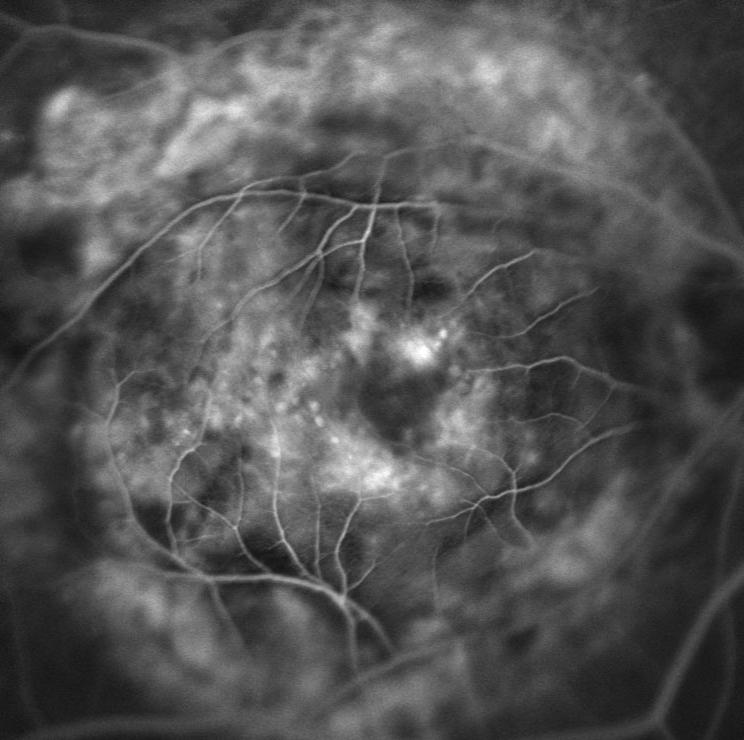

Indocyanine Green Angiography

Vogt-Koyanagi-Harada Disease

Nipan Yodmanee

Mettapracharak Watraikhing Hospital

Nakhon Prathom, Thailand

BEST OF PRINT DIVISION